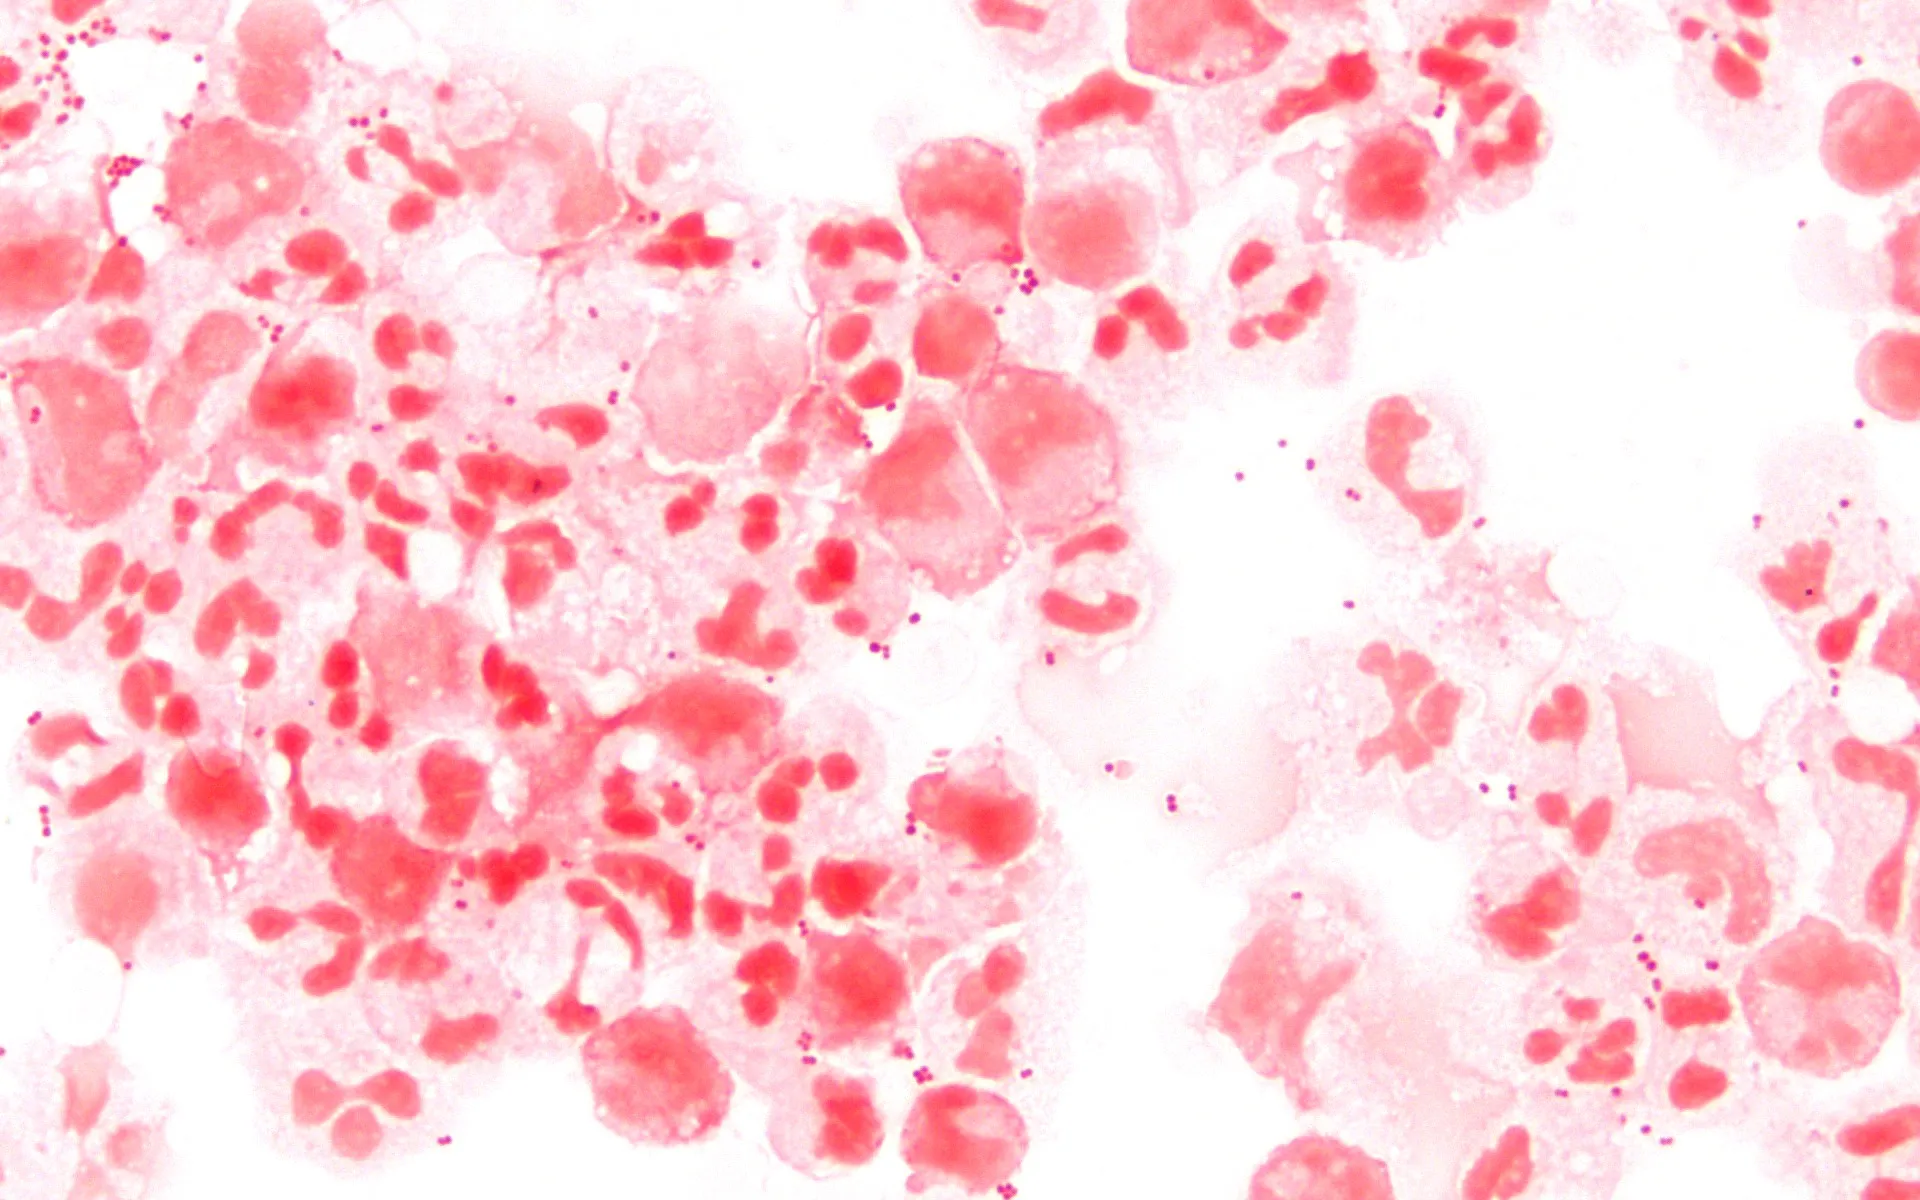

As meninges são membranas que envolvem o cérebro e a medula espinhal. A doença acontece quando essas membranas inflamam. Geralmente, microrganismos como bactérias e vírus são os principais causadores. Contudo, alergias a remédios e até alguns tipos de câncer também podem provocar a inflamação. A condição pode ser confundida com uma gripe comum no início. No entanto, suas consequências são bem mais sérias.

A meningite pode ser causada por diferentes agentes, como bactérias, vírus, fungos e parasitas, segundo o Ministério da Saúde. Ela se transmite por meio de pequenas gotas de saliva de uma pessoa infectada. Essas gotículas chegam às mucosas do nariz ou da boca de alguém saudável. Isso ocorre, por exemplo, ao tossir, espirrar ou liberar secreções respiratórias.